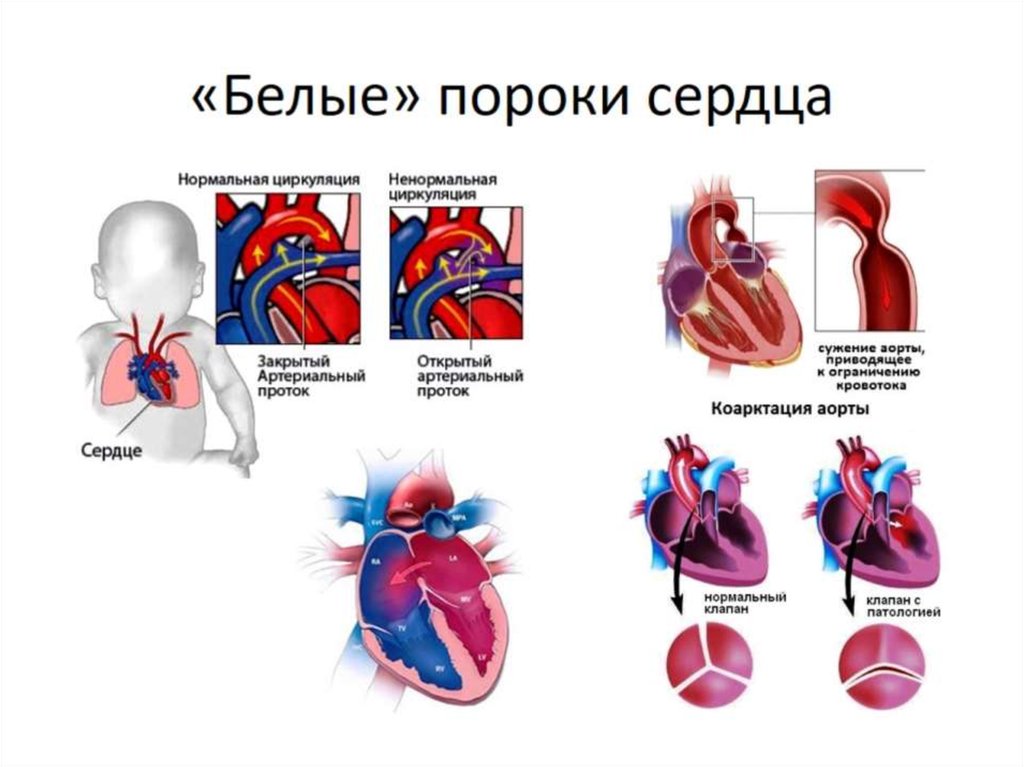

Пороки сердечно-сосудистой системы: виды и признаки